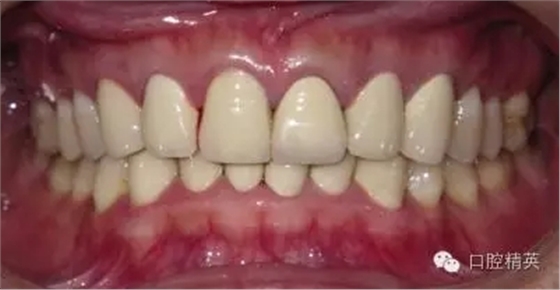

關(guān)于基礎(chǔ)治療。牙周治療和根管治療是美觀修復(fù)的基礎(chǔ)。根據(jù)術(shù)前檢查,常規(guī)先行全口潔治,必要時(shí)局部深層次的牙周治療,待牙周情況穩(wěn)定后,再考慮牙體預(yù)備與取模(見(jiàn)圖1、2)。在牙周炎未控制或牙齦紅腫的情況下,是不可能預(yù)備好牙齒,不可能取得清晰的印模,更談不上成功的美觀修復(fù)。

LAVA 全瓷冠強(qiáng)度高,顏色自然,邊緣高度密合,切端可見(jiàn)半透明感,整體效果理想,與修復(fù)前(見(jiàn)圖1)相比取得了醫(yī)患均滿意的效果。